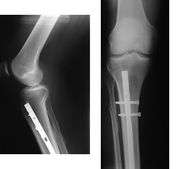

- Osteosynthesa znamená operační řešení, při kterém je kost zpevněna nejčastěji kovovým materiálem, kterým je nějaký druh nerezové oceli nebo titanu, který se po čase buď vyjme, nebo někdy i ponechá. Existuje řada metod, od jednoduchých cerkláží ocelovými dráty, přes šrouby doplněné dlahami až po nejrůznější systémy hřebování s předvrtáváním nebo bez něj (hřeb znamená navlečení nejčastěji dlouhé a duté kosti na pevný a dlouhý ocelový profil, který je na konci zafixován šrouby. Po čase se šrouby na jednom zpravidla distálním (vzdáleném) konci vyjmou, čemuž se říká dynamizace).

- Zevní fixace je navrtání speciálních hřebů někdy se závity na konci do kostních úlomků skrze kůži a jejich upevnění vně končetiny do zevního fixatéru (nejlépe si ho představíte jako stavebnici Merkur, do které zafixujete hřeby a můžete s nimi různě manipulovat a ve vhodné poloze to všechno zafixujete). Existuje řada tuzemských i zahraničních systémů, což platí pro všechny typy operačních metod.